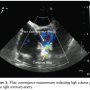

A 53-year-old female with hypertension and obesity presented with exertional dyspnea and chest pain which started about a year ago, and has been worsening with time. She had an unremarkable physical examination, including normal heart sounds. Her cardiac evaluation included a transesophageal echocardiography, which showed a large, tortuous right coronary artery (RCA) abutting the coronary sinus (CS) (Figures 1 and 2; Videos 1 and 2 available at invasivecardiology.com). The flow convergence measurement showed high

volume flow in the RCA (Figure 3; Video 3 available at invasivecardiology.com). Other significant findings included left ventricular hypertrophy, left atrial enlargement, as well as mild right atrial (RA) and ventricular (RV) enlargement and dysfunction. Her left ventricular ejection fraction (LVEF) was well preserved at 65%. For further evaluation, coronary angiography was obtained. It demonstrated a massively dilated right coronary artery (RCA) measuring up to 14 mm in diameter, with a fistulous connection to right atrium (RA) (Figure 4;